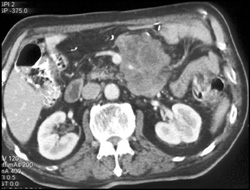

Splenic Laceration